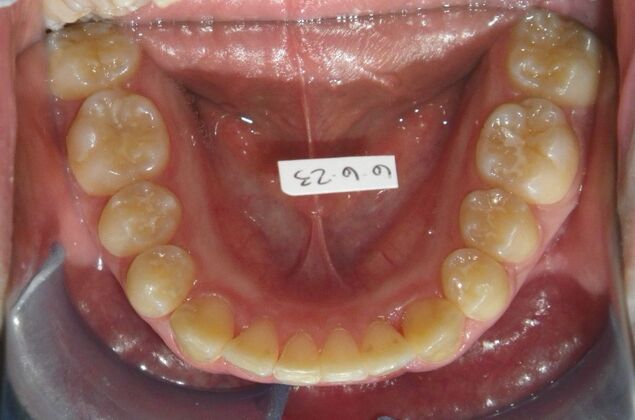

Patient presents with constricted upper and lower arches that will need expansion as well as slenderizing (IPR) to correct upper and lower anterior crowding.